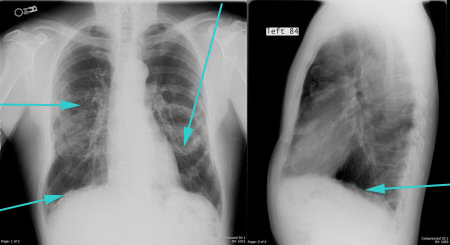

MRI angiography, although accurate, is rarely indicated in the acute setting of aortic dissection because it is difficult to obtain.[Figure caption and citation for the preceding image starts]: PA and lateral CXR showing calcified pleural plaquesFrom the collection of Dr Ami Rubinowitz; used with permission [Citation ends].